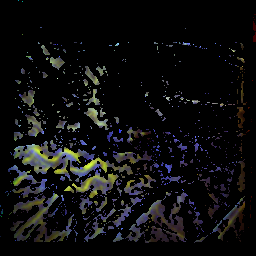

Patient with age-related macular degeneration, dry form

time of the maximum: 50.4 f ± 14.3%visual acuity: 0.30